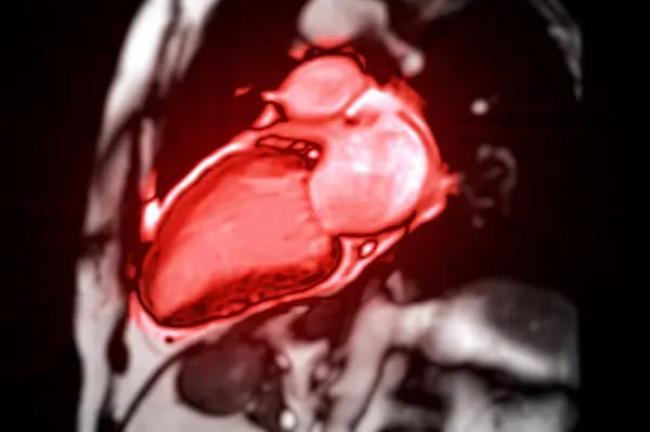

Серце — найскладніший орган для візуалізації. Воно постійно рухається, скорочується 60-100 разів на хвилину, змінює форму з кожним ударом. Традиційні методи — ЕКГ, ехокардіографія, холтер — дають важливу інформацію, але не бачать усіх деталей. МРТ серця відкриває новий рівень розуміння серцевої діагностики.

Основна складність МРТ серця — синхронізація з серцевим ритмом. Звичайне МРТ показало б розмиті контури через рух. Тому використовують ЕКГ-синхронізацію: апарат робить знімки в конкретну фазу серцевого циклу — систолу або діастолу. З сотень серцевих ударів складається єдине чітке зображення.

Існує кіне-режим, коли томограф створює відео серцевого скорочення. Кардіолог бачить, як рухаються стінки шлуночків, чи всі сегменти скорочуються синхронно, чи є зони акінезії (нерухомості) після інфаркту. Це дає розуміння стану функції, а не лише анатомії.